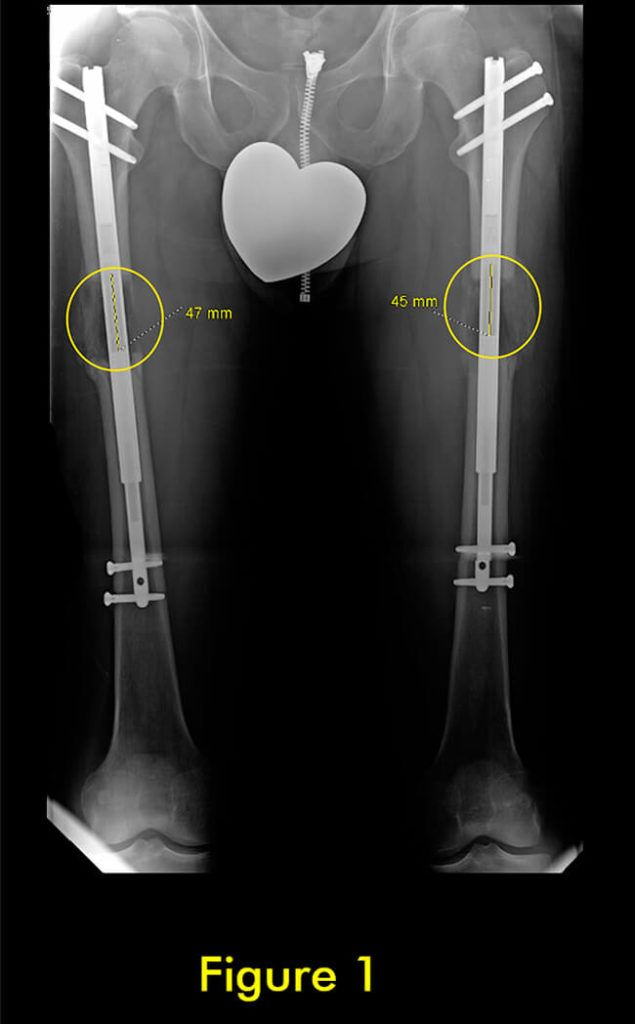

过早合并示意图1

图1:延长量细微差异

过早合并示意图2

图2:X光片确认诊断